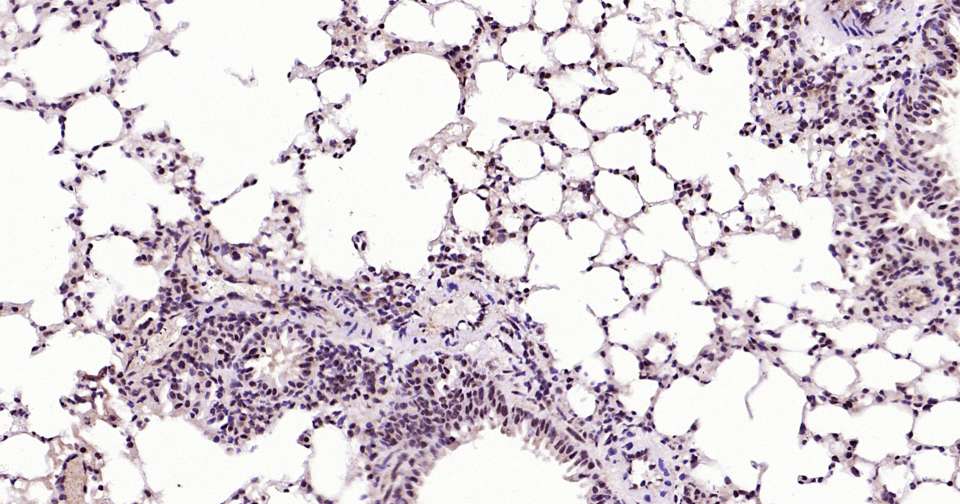

Immunohistochemical analysis of paraffin embedded rat lung tissue slide using IHC0387 (phospho-STAT3 (Ser727) Kit).